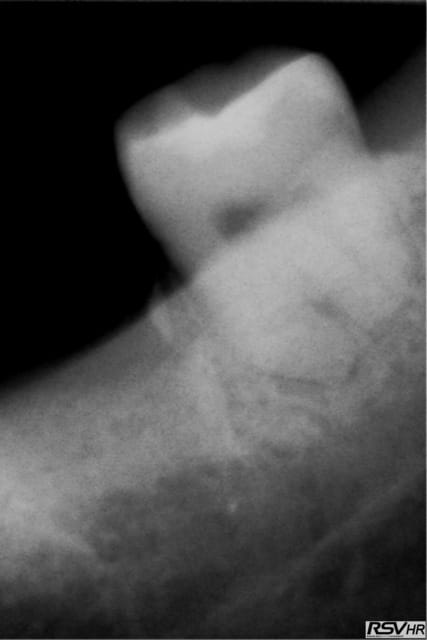

et non pas à 8 semaines je l'ai extraite le 19.11.2011 donc c'est plus et je te joins une retro avant l'extraction la dent ne présentais pas de lésion paro enorme donc je ne vois pas pourquoi un TG se serait développé plus facilement.

J'ai du utiliser un fraise zekrya et j'ai mis dans l'aveole des éponges hémostatiques collageniques.

Lev3 a36qqm - Eugenol

c'est pas parce que t'as mis des éponges que tu n'as pas eu une petite alvéolite qui a retardé la cicat (chose fréquente quand on utilise une fraise pour faire une alvéolectomie/séparation...)

à 4 mois amha çà devrait être plus dense si tout était normal...